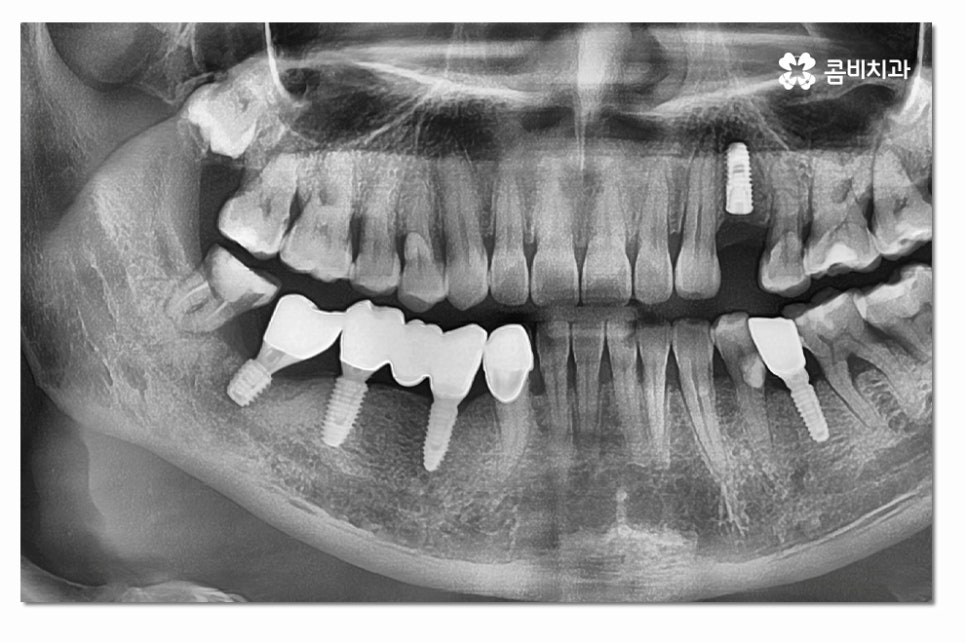

오늘 보여드릴 환자분은 어금니 임플란트 치료를 하게 된 사례로

일반적으로 어금니는 저작 기능을 중점적으로 수행하기 때문에

노화가 진행되면서 치아 사이에 틈이 생기고, 그 틈으로

음식물이 끼면서 치아와 잇몸 경계 부분에 치석이 쌓이기 쉬우며

사랑니로 인해 관리가 잘 안될 경우 충치나 염증으로

인해서 어금니가 손상될 수도 있어요.

어금니의 손상은 생활 습관에 따라서 구분이 되기도 하는데

너무 딱딱한 음식을 자주 섭취하거나 이갈이, 이 악물기 등의

습관으로 인해서 치아가 손상되는 경우가 있으며

청결관리가 잘되지 않아서 충치 및 치주질환이 발생되는 경우도 있는데요.